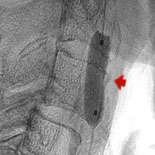

Fig 1: An anterior-posterior view of the left carotid artery in the neck shows the narrowing of the artery.

The cutting edge treatment is to insert a carotid filter balloon which is an umbrella like device used to catch debris as the artery is being opened. Fig.1 shows Ralph's narrowing of the left carotid artery. Fig.2 shows the device being inserted in Ralph's artery. In fig.3 the carotid balloon's up showing inflation of the balloon which opens the blocked artery. A stent (fig.4) which is a metallic cage is placed in the artery to keep it opened.